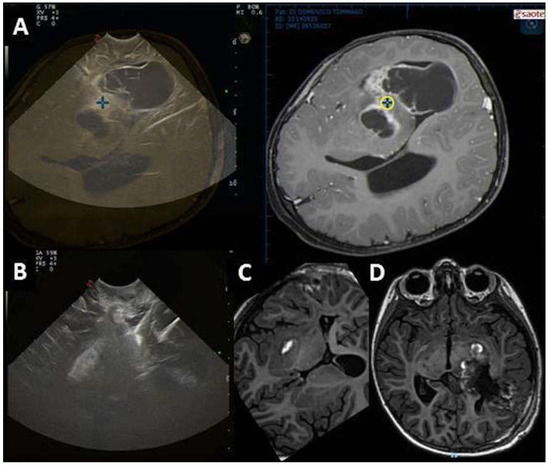

| EOR | Open ventricle |

|

| EOR | Artifacts |